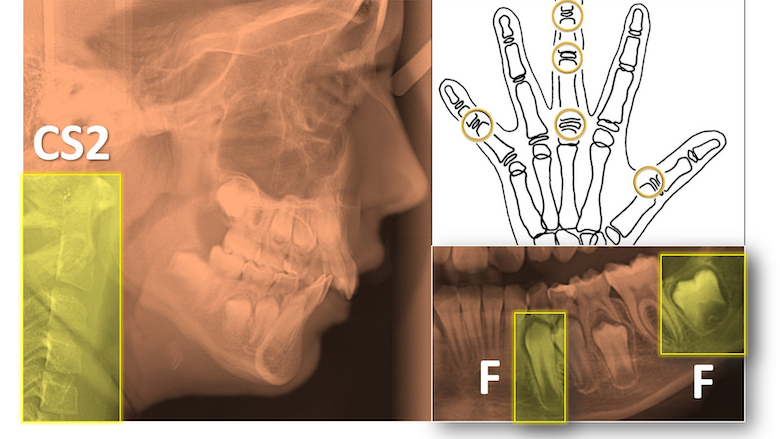

Esta columna no es el lugar donde presentar la evidencia científica, pero sí quiero llamar la atención sobre el renovado interés que tiene la calcificación de los dientes (canino permanente inferior y segundos molares permanentes inferiores) y la columna cervical (perfectamente evaluable en la teleradiografía lateral) en el cálculo de la edad ósea del paciente. Recomiendo revisar desde los trabajos más clásicos de Coutinho (1993) sobre la calcificación del canino inferior, a los más actuales de Bittencourt (2018), Fernandes-Retto (2019) o Mollabashi (2019). El momento inicial ideal de uso de la aparatología funcional coincidiría con el estadío F en el canino y el CS2 en las vértebras cervicales. Demoledor para los que proponen tratamientos precoces y largos en las Clases II mandibulares resulta el ya clásico trabajo de W R Proffit y JF Tulloch (2004), donde demostraba cómo en este tipo de maloclusiones, los tratamientos tempranos no suponían ninguna ventaja (en términos de acortamiento de la segunda fase, necesidad de extracciones o cirugía ortognática), frente a los realizados en una sola fase iniciada al principio de la pubertad. Este es un principio básico, nuestra regla de oro: cualquier tratamiento de primera fase ha de suponer una ventaja significativa en el resultado final del tratamiento.

El momento inicial ideal de uso de la aparatología funcional coincidiría con el estadío F en el canino y el CS2 en las vértebras cervicales.